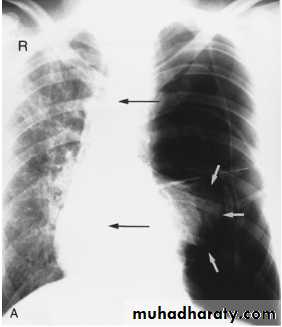

On a posteroanterior chest x-ray (A), the left hemithorax is very dark or lucent because the left lung has collapsed completely (white arrows).The tension pneumothorax can be identified because the mediastinal contents, including the heart, are shifted toward the right, and the left hemidiaphragm is flattened and depressed. A computed tomography scan done on a different patient with a tension pneumothorax (B) shows a completely collapsed right lung (arrows) and shift of the mediastinal contents to the left.

Tension Pneumothorax. Portable chest film in a 43-year-old woman with ARDS shows a large right pneumothorax with mediastinal shift and ipsilateral diaphragmatic depression, suggesting tension.

Air was evacuated under pressure during emergent placement of a right chest tube.